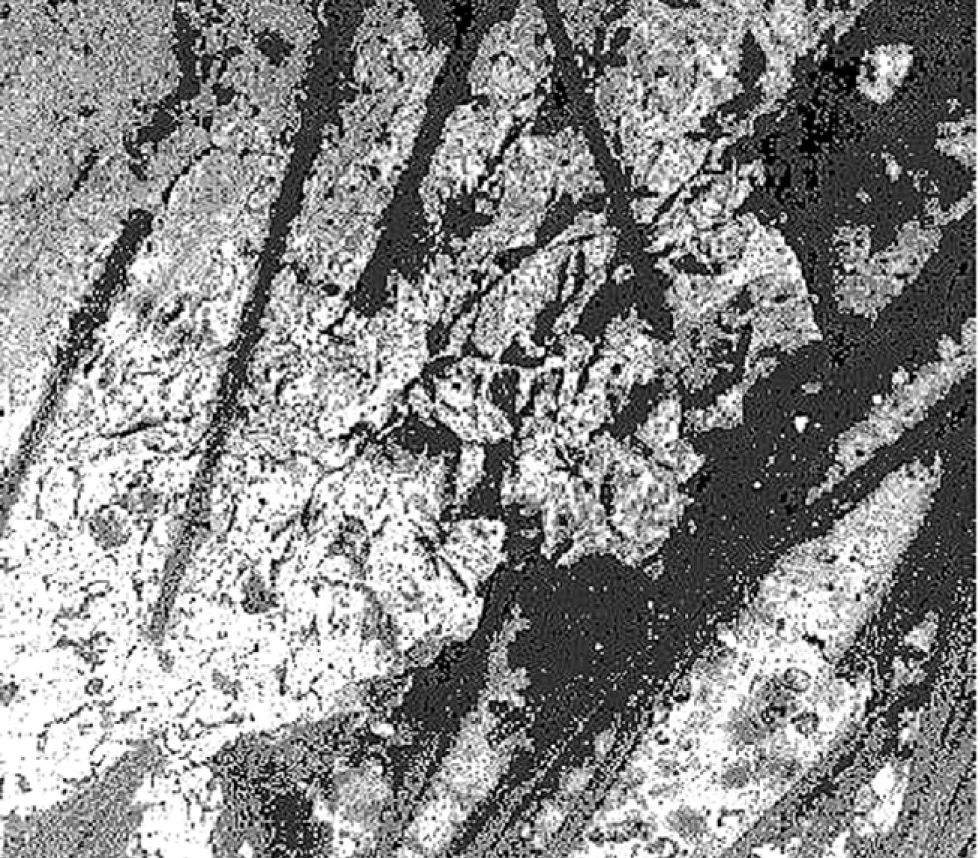

In the second study group, 60% had violations of the marginal fit of the restoration. On the electron diffraction pattern, at the border of the restoration, inclusions (Fig. 6) from microbrush fibers were observed. We hypothesize that the Prime&Bond Universal adhesive system (Dentsply) affected the fibers and caused them to fall out of the plastic rod.

In the third group with samples from OptiBond Universal (Kerr) and "OptiShade" (Kerr), the fit was broken in 10% of cases (Fig. 7).